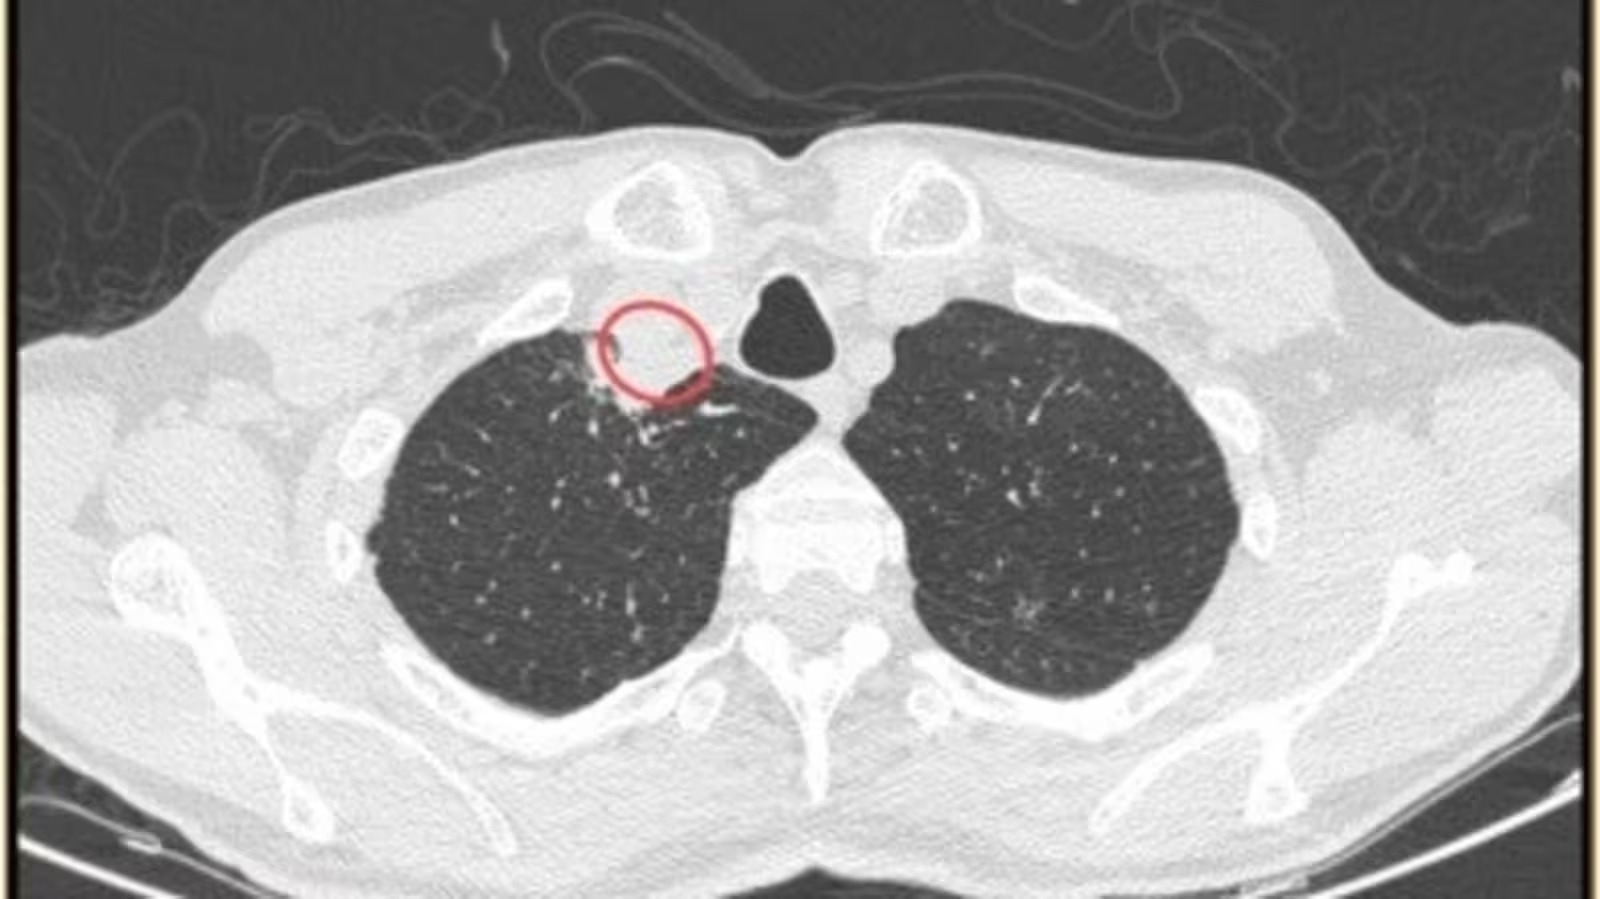

They identified a neck abscess in the man and performed a surgical procedure to drain it and said, "After the surgical procedure, an X-ray examination showed no unusual findings, and the patient was prescribed a round of antifungal medication."